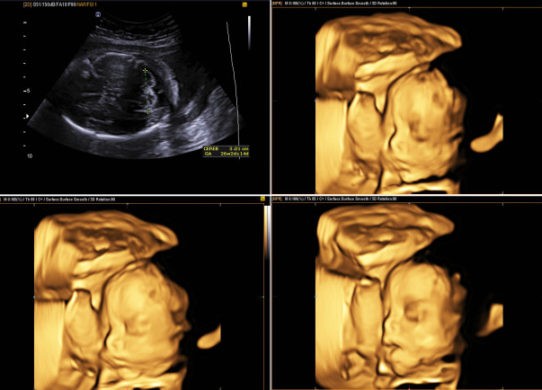

I controlli in gravidanza sono essenziali per monitorare il buon andamento della gestazione ed il corretto sviluppo del feto. Oggi, le tecniche sono…